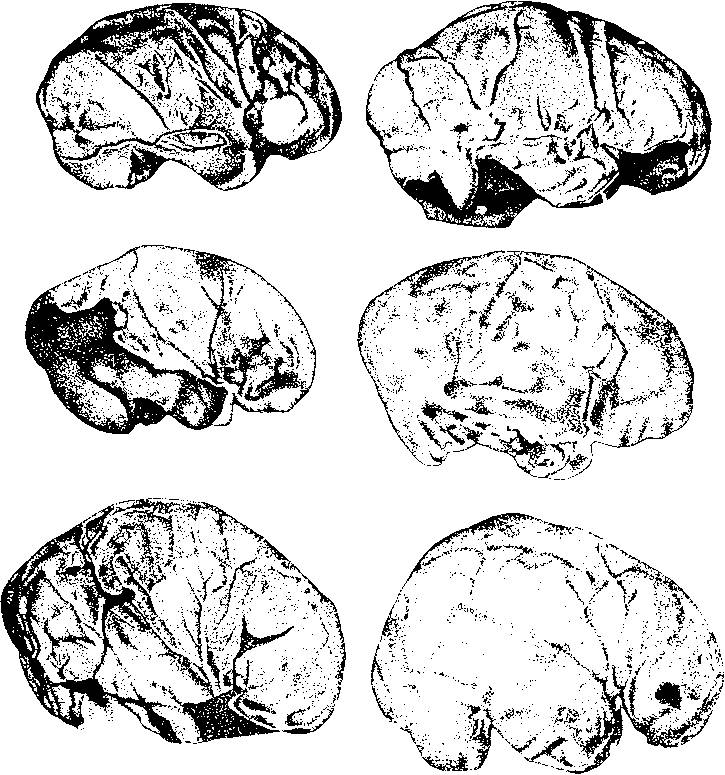

Давайте взглянем на коронарный срез через лобные доли мозга.

Мы увидим, что сложнорасположенные изгибы коры головного мозга, мягко говоря, неравновысотны, и что в петлях срезов любой из извилин находится substantia alba (белое вещество). Это то, что видно глазу при простом фронтальном срезе (илл. 21а).

Отпрепаровка покажет, что снизу в кору вплетаются миллиарды волокон мозолистого тела ( corpus callosum) – структуры сверхнежной и сверхсложной (илл. 21Ь). Все это, естественно, при добросовестной экстирпации частично удаляется вместе с корой или фатально поражается.

Илл. 21а. Фронтальный срез мозга. Видны сложнорасположенные изгибы

коры головного мозга, в петлях срезов любой из извилин находится

substantia alba (белое вещество) (по Блинкову)

Илл. 21Ь. Волокна мозолистого тела (по Блинкову)